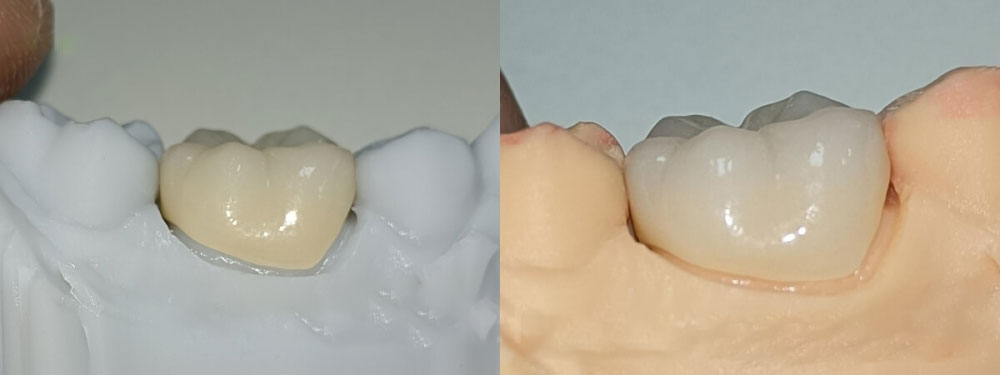

The grey color 3D printed model is working model, while the oringe one is study model.

As we can see, the margin of the full zirconia crown is perfect on the working model and the study model.

Full zirconia crowns